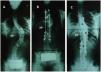

Se intervino a todos los sujetos mediante una artrodesis instrumentada posterior híbrida con tornillos pediculares distales y ganchos proximales (figs. 1 y 2). El sistema de instrumentación empleado fue el Moss Miami® (DePuy) en 13 sujetos y el Monarch® (DePuy) en otros 13 sujetos. En primer lugar, se insertaron los tornillos pediculares en la zona lumbar o torácica baja tras localizar las referencias anatómicas adecuadas1,20–22; se realizaron comprobaciones mediante fluoroscopia intraoperatoria. A continuación, se labraron los lechos para los ganchos de la parte cóncava: habitualmente se comenzó por la concavidad de la curva mayor (por lo general, la curva torácica) en la vértebra estable superior a la vértebra límite superior y 2 vértebras más abajo se aplicaron 2 ganchos pediculares orientados hacia la vértebra proximal; un tercer gancho se insertó hacia la vértebra distal en el ápex o en la vértebra inferior a ésta. Seguidamente, la barra de la concavidad se colocó premodelada según las curvas fisiológicas de cifosis torácica y lordosis lumbar realizando distracción en los distintos segmentos patológicos y, según los casos, con maniobras de desrotación y torsión in situ de la barra en busca de una óptima corrección de la deformidad. Como siguiente paso se implantaron los ganchos de la parte convexa: habitualmente se cerraba el sistema con un gancho (laminar o transverso) orientado hacia la vértebra distal en la vértebra estable superior a la límite superior y otro gancho hacia la vértebra proximal en la vértebra inmediatamente inferior, se insertaba un tercer gancho hacia la vértebra distal en la vértebra ápex y seguidamente se realizaban maniobras de compresión de la curva tras colocar la barra (también premodelada de manera fisiológica).

Corrección coronal en uno de los sujetos con una curva de tipo i de Lenke. Se indican los respectivos ángulos de las curvas según Cobb, las vértebras limitantes (sexta vértebra torácica y primera vértebra lumbar) y el ápex (novena vértebra torácica). A) Radiografía prequirúrgica. B) Posquirúrgica inmediata. C) A los 3 años. Se produjo una corrección inmediata del 63% que descendió hasta el 54% tras la pérdida de 6° de corrección y su posterior estabilización. La inclinación lateral (bending test) preoperatoria era de 48° (el 27% de corrección en inclinación lateral). No se observó seudoartrosis.